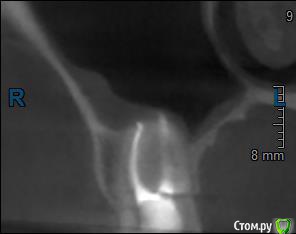

Здравствуйте! Верхний правый шестой зуб пломбировали 3 месяца назад. Примерно месяц назад он начал ныть, после насморка, сначала периодами, а теперь почти постоянно. При постукивание (ощущается не совсем так, как другие зубы) и пальпации десны он не болит. 2,5 месяца назад удаляли кисту из гайморовой пазухи. Может ли быть это какое-то воспаление и есть ли вероятность устранить его какими-нибудь антибиотиками, если да, то как, или может удалить зуб? Если есть воспаление, то какие могут быть последствия если не удалить зуб?

(Снимки с КТ, первые 8(Image) - сделаны сейчас,по 4 в разных проекциях, вторые 8(Before) - сделаны 5 месяцев назад до удаление кисты и повторного пломбирование зуба( до повторного пломбирование он реагировал на горячее, был запломбирован 3 года))